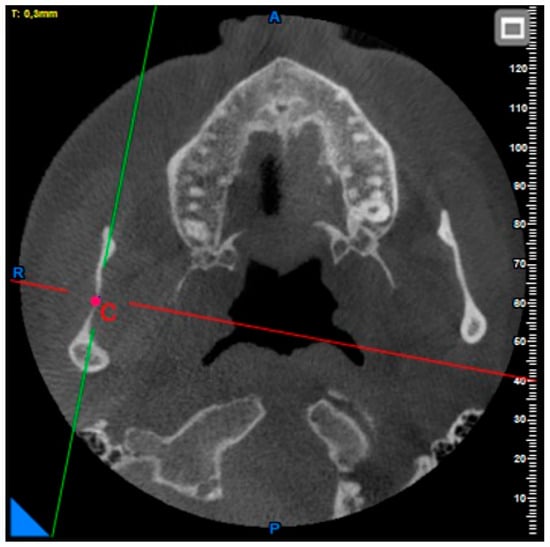

A Morphometric Evaluation of the Mandibular Condyle, Coronoid Process, and Gonial Angle: Age and Gender Differences in CBCT Imaging

2. Materials and Methods